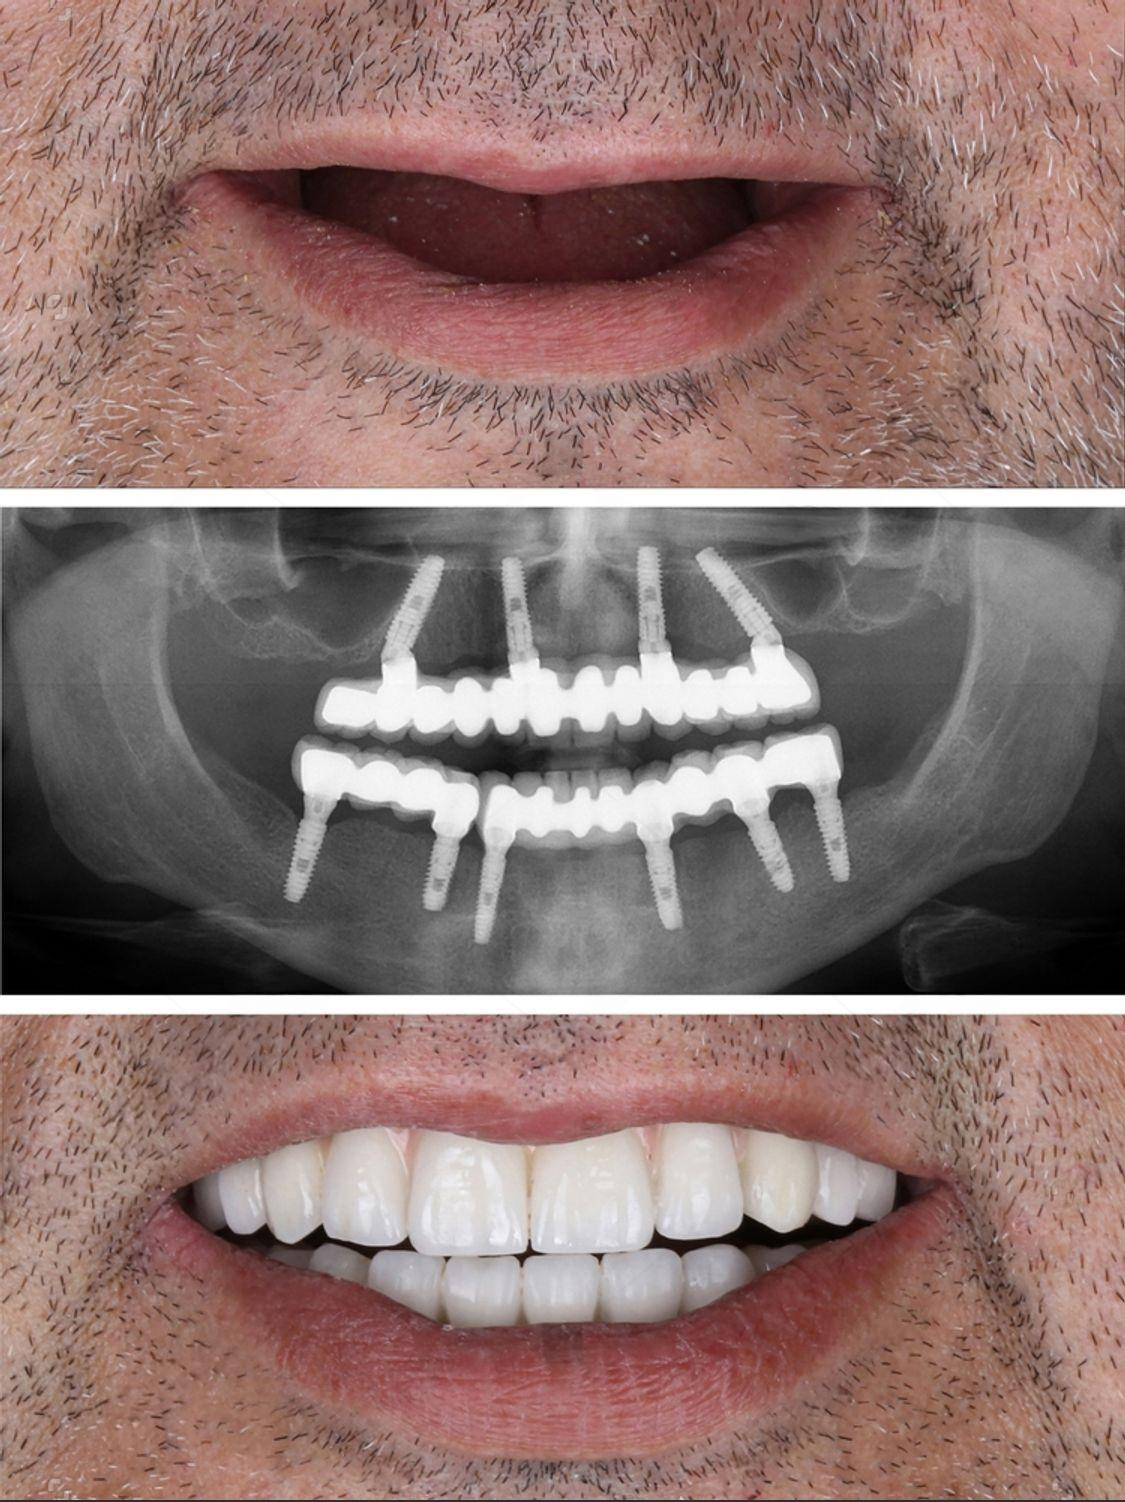

Real Results. Real Confidence.

At Al Rayashi Dental Center, we believe that every smile tells a story — and we’re proud to be part of so many incredible journeys. Our Smile Transformations page showcases real patients who have trusted us to restore their confidence and enhance their dental health.

From subtle refinements to dramatic changes, these before-and-after cases highlight the power of expert care and advanced dental technology.

Smile Transformations